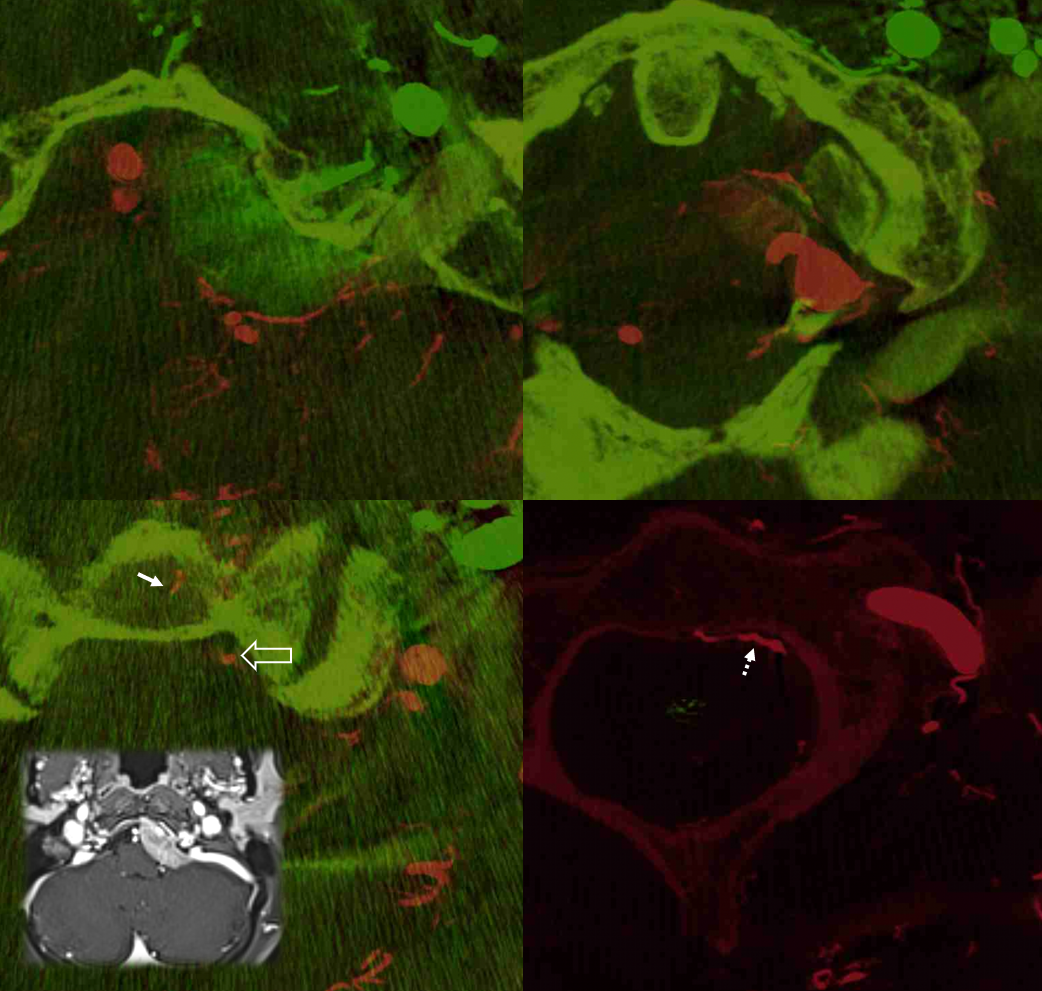

Often overlooked, and just like elsewhere in spine, the odontoid/epidural arcades supply adjacent nonneural structures — dura and bone — C3 C2 and C1 in this case. Odontoid arcade (open arrows), transversely oriented epidural branches (dashed white arrows), intraosseous branches (solid white arrows), and ventral bone supply from C2/C3 segmental branches (dashed black arrows)

Without annotations below

Many cases, like the one above, are derived from embolization of meningiomas, allowing for subselective odontoid catheterizations. Below are fusion DYNA CT images of this case, showing the target lesion. Most of the supply is derived from hypoglossal division, seen via the green-colored left ECA injection. The vert injection is in red, opacifying the arcade among everything else vertebrobasilar.